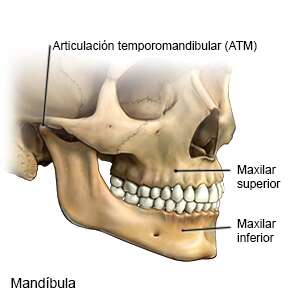

La fractura del maxilar ocurre cuando se rompe el hueso y los dientes cambian su disposición de encaje, y no se puede abrir la boca a su abertura normal, generalmente la boca se desplaza cuando está se abre o se cierra, casi siempre este tipo de fractura ocurre en la parte inferior del maxilar.

Esta fractura puede provocar fallas en la visión, ya que cerca de las mandíbulas se insertan los músculos de los ojos, eso produce insensibilidad cerca de la piel de los pómulos y que está debajo de los ojos, y genera irregularidades en la mejilla.